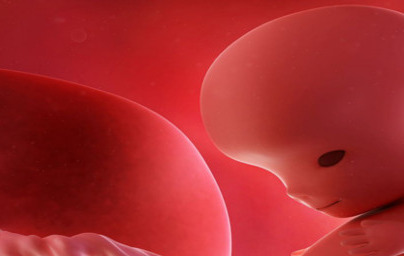

11. teden nosečnosti

Čeprav je plod komaj velikosti kumkvata (drobnoplodne pomaranče) in tehta zelo malo, je v tem obdobju zaključil najbolj kritično fazo razvoja. Spoznajte 10. teden nosečnosti in si preberite celoten opis...

Kaj se dogaja v 10. tednu?

Čeprav je plod komaj velikosti kumkvata (drobnoplodne pomaranče) in tehta zelo malo, je v tem obdobju zaključil najbolj kritično fazo razvoja. To je začetek fetalne dobe, čas, ko tkiva in organi v telesu hitro rastejo in dozorijo.

Plod prične požirati tekočino. Vitalni organi, vključno z njegovimi ledvicami, črevesjem, možgani in jetri pričnejo delovati, čeprav se bodo med nosečnostjo še naprej razvijali.

Če bi si lahko ogledali notranjost maternice, bi opazili tudi drobcene nohte na prstkih rok in nog in celo dlake, ki rastejo na površini kože.

Plod lahko premika svoje okončine. Roke so na zapestjih upognjene in se nahajajo nad srcem, noge pa so precej dolge. Skozi prosojno kožo je jasno viden obris hrbtenice. Čelo je zaradi možganov videti precej napihnjeno in se nahaja zelo visoki na glavi. V prihodnjih tednih se bo velikost ploda podvojila.